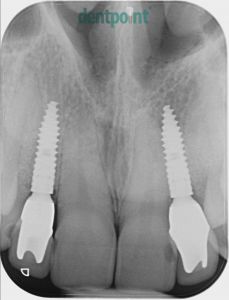

Régi implantátumok cseréje, fémmentes koronák felhelyezése

Fiatal hölgy páciensünk a 10 évvel ezelőtt behelyezett implantátumainak csontpusztulása és ínyének visszahúzódása miatt keresett fel minket. A régi implantátumok eltávolítását követően újakat helyeztünk be, és ínyplasztikai kezeléssel, valamint cirkónium egyéni implantátum fejekre készített e.max fémmentes kerámia koronákkal adtuk vissza páciensünk elégedett mosolyát.

1) Kiindulási helyzet röntgenfelvétel

2) Implantátumcsere utáni röntgenfelvétel